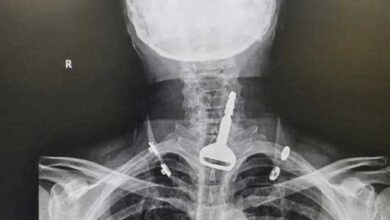

بالصّورة – ابتلع مفتاح سيارته

أنقذ فريق طبي بمدينة القنفذة السعودية أربعينيا من الموت بعد استخراج مفتاح سيارة عالق بالجهاز التنفسي في عملية استغرقت 15…